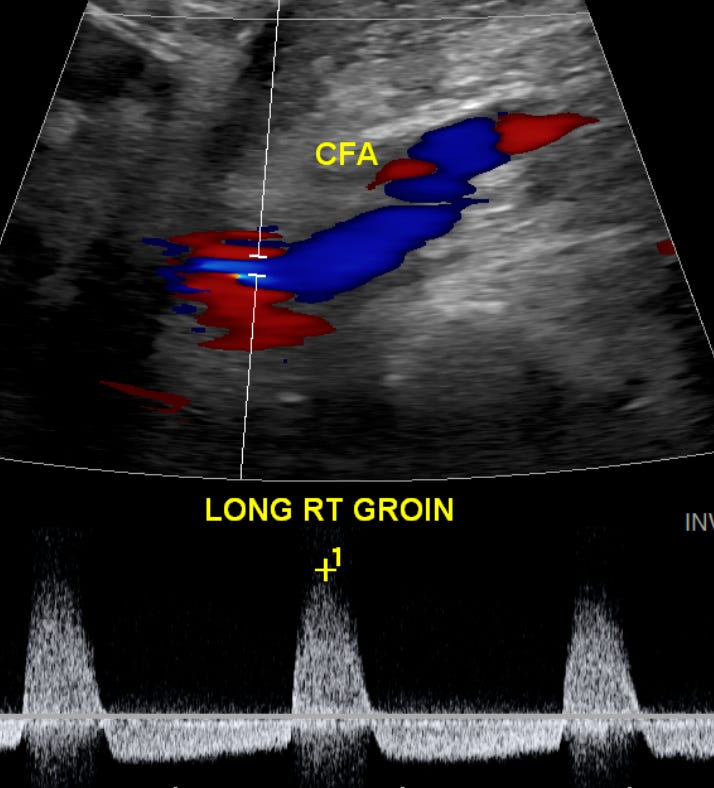

When using pulsed wave Doppler, the classic finding is the visualization of alternating “systolic” flow spikes above and below the baseline. Both the Yin-Yang sign on a color Doppler and the alternating spikes above and below the baseline with pulse wave Doppler are helpful in differentiating a pseudoaneurysm from a simple hematoma, which would not demonstrate internal flow.”

And here is the pulse wave doppler showing alternating “systolic” flow spikes above and below the baseline: